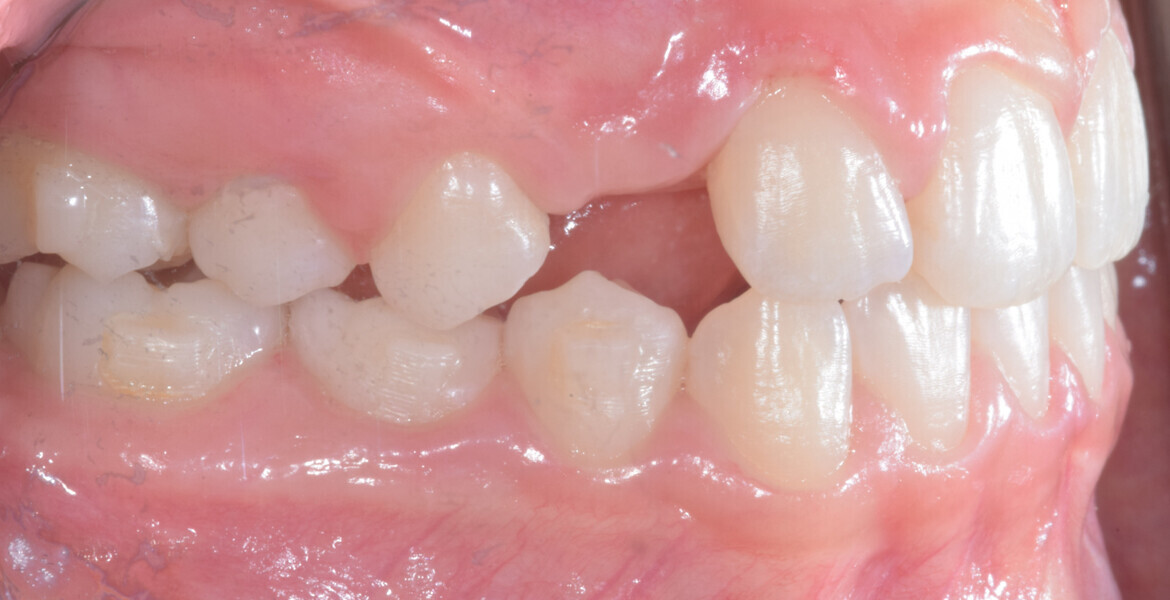

A 14-year-old female patient presented with the chief complaint of midline deviation and dental crowding in both arches. Facial analysis showed a hypodivergent growth pattern, a normal nasolabial angle, a harmonious profile and proper chin projection. Clinical examination revealed a Class III skeletal relationship (ANB = 0°) and Class I molar relationship. The maxillary right canine was absent, and this had led to space loss and mesial drift of posterior teeth on the right side, resulting in a slight Class II molar relationship. The maxillary left canine had erupted in a high position. The mandibular arch displayed crowding despite the agenesis of the right second premolar and the persistence of the primary molar (Figs. 3–11). The radiograph showed the probably premature loss of the maxillary right primary canine and consequently impacted maxillary right permanent canine, and the agenesis of the mandibular right second premolar and the mandibular right third molar (Fig. 12).

Cephalometric analysis showed normal incisor inclination (U1–PP = 112°) and slightly uprighted mandibular incisors (IMPA = 88°), consistent with dental compensation commonly observed in Class III skeletal malocclusions. Cephalometric analysis confirmed a reduced lower anterior facial height associated with a hypodivergent pattern (Figs. 13 & 14).